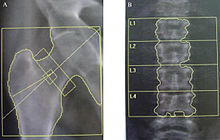

Dual-energy X-ray absorptiometry (DXA, previously DEXA[1]) is a means of measuring bone mineral density (BMD) using spectral imaging. Two X-ray beams, with different energy levels, are aimed at the patient's bones. When soft tissue absorption is subtracted out, the bone mineral density (BMD) can be determined from the absorption of each beam by bone. Dual-energy X-ray absorptiometry is the most widely used and most thoroughly studied bone density measurement technology.

The DXA scan is typically used to diagnose and follow osteoporosis, as contrasted to the nuclear bone scan, which is sensitive to certain metabolic diseases of bones in which bones are attempting to heal from infections, fractures, or tumors.